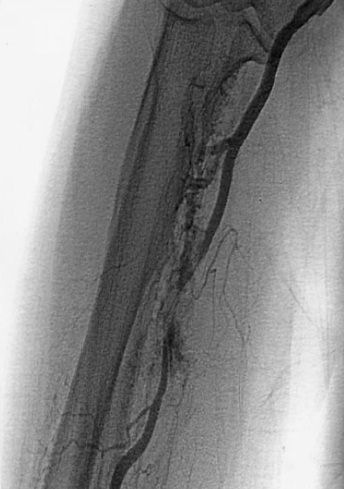

桡动脉穿孔:主要由于桡动脉走行迂曲或成袢;桡动脉痉挛;如果怀疑进行血管造影。桡动脉损伤的处理如下图[9]:

![]() 桡动脉穿孔 ![]() 鞘管前进 ![]() 最后造影结果